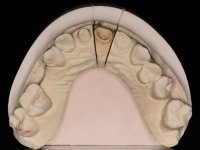

Endodontic treatments were performed and a metalic non screwed intra radicular post was placed on tooth 1.1. An alginate impression was made for laboratory confection of a reinforced acrylic provisional bridge, with teeth 1.1 and 2.2 as abutments and 2.2 as a pontic. After preparation of tooth 1.1 and root preparation of 2.1, the bridge was relined in mouth with self-polymerizable acrylic using a metal post for further retaining the prepared root canal on 2.1. Tooth 2.2 was cut at the gingival level to function as support. In the same session, the impression of the root canal of the 2.1 was made for the laboratory confection of a cast post and core. A double mixture technique with plastic tutor was used after previous canal vaseline with endodontic file and cotton. The provisional bridge was provisionally cemented and the cast post and core was made in the laboratory. Cast post and core cementation was made with resin-reinforced glass ionomer cement and the provisional bridge had to be readjusted to the new situation by removing the post at the site of 2.1. After careful surgical planning, a dental implant was placed, simultaneously with extraction of the root of tooth 2.2. The provisional bridge was placed by resting on the healing screw placed in the implant. The respected osteointegration period was 12 weeks, during which the provisional bridge was relined twice. After complete maturation of hard and soft tissues, definitive impressions were made. The gingival retraction technique was applied with an impregnated retraction cord and impression was performed using double mixture, open tray impression technique. A custom precious metal abutment implant was prepared in the lab, along with 3 metal caps to be used as infrastructures for the metal ceramic crowns. Particular care was taken in the confection of the cervical finishing line of the implant abutment, in order to follow the soft tissues emergence profile. Proof of infrastructures was done in the mouth being evaluated clinically and imagiologically. Collection of color information was done by the ceramist at the office. Ceramic was applied in the laboratory and the finished work was placed in the mouth after approval by the patient. Definitive cementation was made with resin-reinforced glass ionomer cement, and the first crown to be cemented was that of the implant, to facilitate removal of the excess.